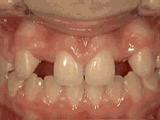

2、牙列不齐,牙齿异位,咬合关系紊乱,影响正常发音和正常咀嚼,经过矫正后是变成这样的~